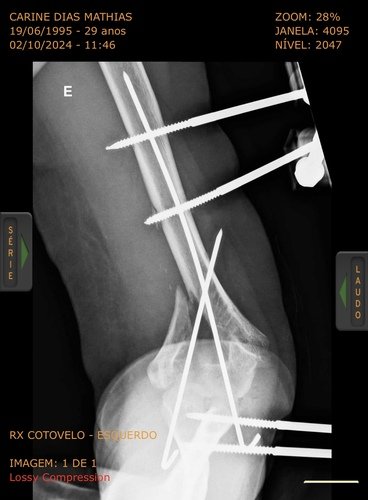

Olá sou Carine e fui vítima do acidente de trânsito ocorrido em 08/09/24 na ponte de integração Santo Tomé/São borja, quebrei em várias partes o cotovelo esquerdo onde precisei passar por uma cirurgia feita em 01/10, porém não obtivemos bons resultados somente com fios tendo a ter que passar por uma nova cirurgia particular para aplicar placas. Sou autônoma e estou sem pode trabalhar, sendo assim venho por meio desta vakinha pedir ajuda, toda ajuda é bem vinda. Desde já agradeço.